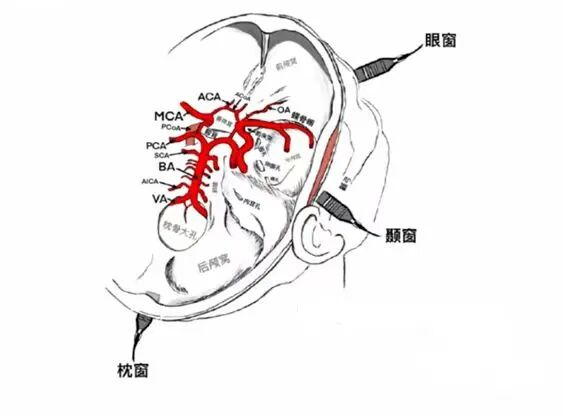

TCCD又称颅内段血管彩色多普勒超声,是一种重要的辅助检查手段,主要用于评估颅内血管的情况,利用超声多普勒技术和脑血管成像技术,以颅骨自然薄弱的部位作为检测声窗(如颞骨嶙部、枕骨大孔、眼眶),通过二维、彩色、频谱多普勒等检查手段评价颅内血管血流动力学的超声检查方法。

(图片来源于网络)